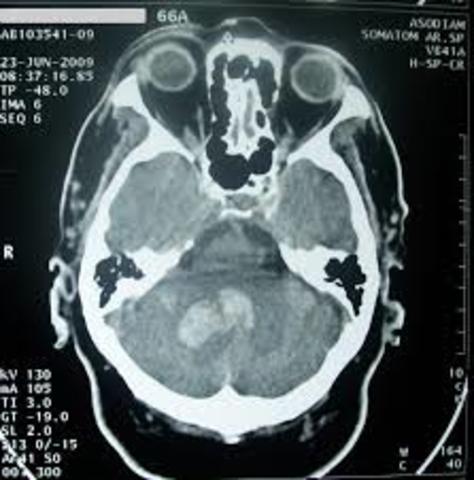

• IMAGENES CRANEALES

IMAGENES CRANEALES

En 1971 se instala en EEUU el primer equipo de tomografía computarizada especializado en

imágenes craneales.